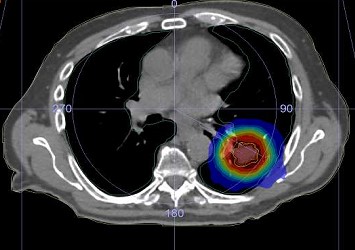

SBRT has been defined by the American College of Radiology (ACR) and the American Society for Radiation Oncology (ASTRO) as the use of very large radiation doses, defined as >6 Gy/fraction delivered in a few (five or fewer) fractions. SBRT has unique radiobiological characteristics that can cause dramatic tumor response, leading to the associated term “ablative” radiation therapy. SBRT requires precise localization of the target volume. “Stereotactic” refers to the fact that SBRT is centered on the target volume and uses online IGRT to localize the tumor in space. The irradiated tissue volume is minimal to reduce toxicity, with a high dose gradient, high conformality, and heterogeneous dose distribution in the PTV. The techniques used can be coplanar or non-coplanar, with IMRT, arc therapy, or cones. The margins are small, dosimetry and dose delivery are complex, and require precise small-field dosimetry.

SABR/SBRT is used with high local control and excellent tolerance to treat primary tumours instead of surgery: lung, prostate, pancreas, liver Hepatocellular Carcinomas, Cholangiocarcinomas, Renal cancer…